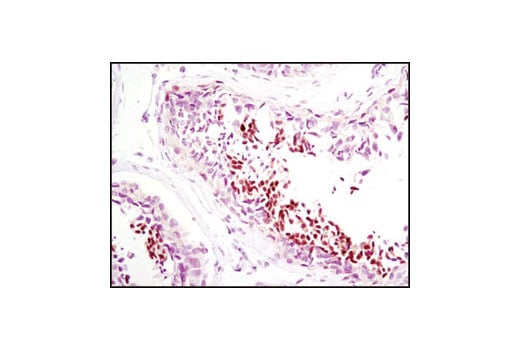

Immunohistochemical analsysis of paraffin-embedded human midline carcinoma using NUT (C52B1) Rabbit mAb.

Immunohistochemistry Image 1: NUT (C52B1) Rabbit Monoclonal Antibody